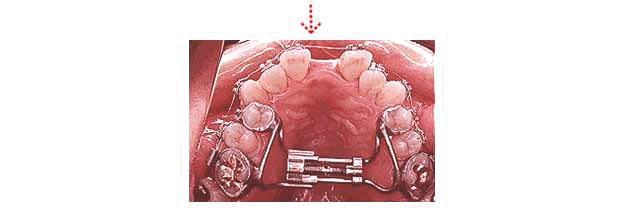

下顎前突症+反対咬合+上顎歯列弓峡窄

Le FortI 型 Corticotomy併用の歯科矯正

Koelle氏法 Corticotomy併用の歯科矯正

コルチコトミーを併用することにより、歯列矯正だけでは困難な症例も治療可能となります。

また治療期間の短縮のために、コルチコトミーを行うことも可能です。